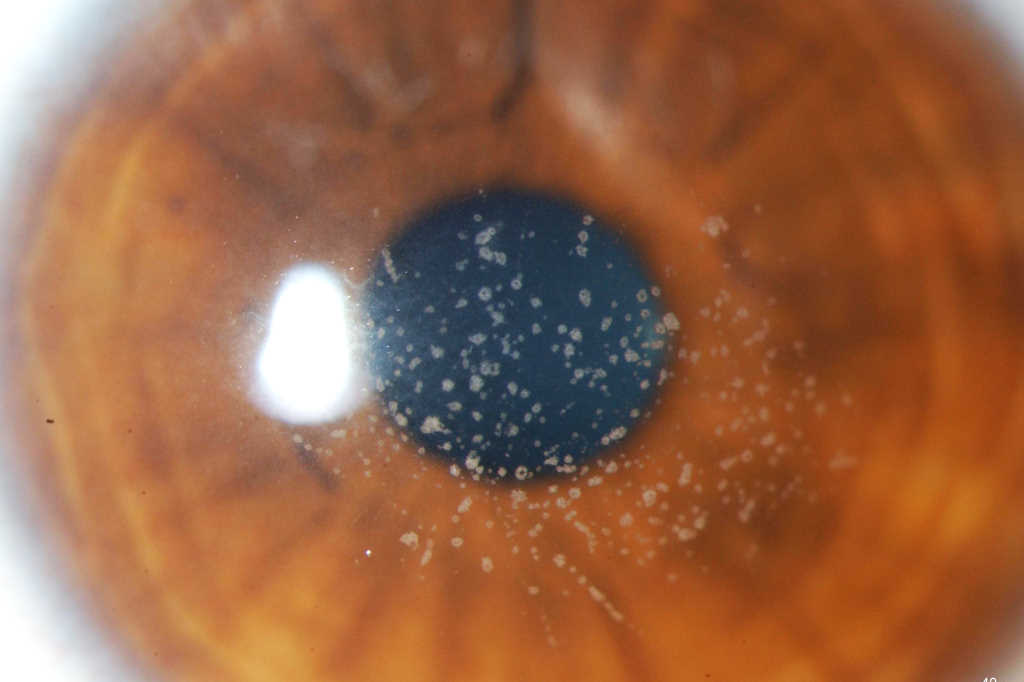

GCD1 is characterised by bilateral deposits in the anterior central stroma appearing as small, discrete, well demarcated, greyish-white opacities, typically appearing during the first or second decade of life. The deposits may first appear as fine dots which later take on a crumb-, ring-, or drop-shaped appearance. These lesions progressively increase in size, number, and may coalesce. Further advancement sees a ground-glass appearance of the cornea develop between lesions. In the early stages, patients normally suffer no discomfort or visual changes, although a subset does suffer erosive episodes. By the fourth decade, visual impairment can begin, typically secondary to opacification of the intervening stroma (Fig 1).

Fig 1a. Central crumb-like stromal deposits with clear intervening stroma

Fig 1b. Confluent breadcrumb granular opacities under direct and retro-illumination

Fig 1c. GCD1 in the same family, with large peripheral-sparing grey-white opacities in the father

Fig 1d. GCD1 in the same family, with a much finer, granular appearance in the daughter.

Credit: Prof McGhee